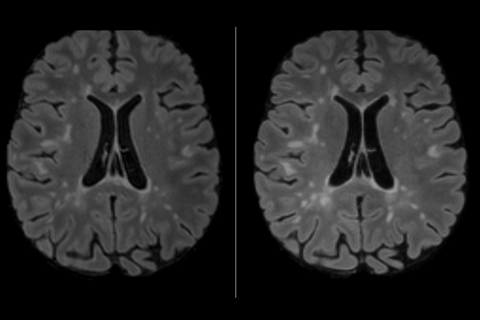

[Appel à volontaires] Etude clinique "OSV-IRM"